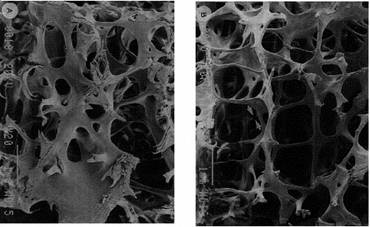

Oasele spongioase mai cunoscute ca oase trabeculare. Matricea structurala osoasa plata este de lonjeron cu maduva in spatiul intermediar (figura 6). Structura lonjeroanelor depinde de locatia lor si de situatia existenta. Lonjeroanele spongioase au, de obicei, 150300 m diametru si forma tridimensionala cu structura reticulara, cu rezistenta optima a raportului de greutate in oasele sanatoase.

Figura 6 Structura osului spongios plat la un adult sanatos, respectiv la unul osteoporotic

In microstructura oasele spongioase au forma oaselor lamelare (figura 5), iar macrostructura oaselor spongioase este dependenta de locatia anatomica. In general, se dezvolta ca raspuns la situatia data. Spre exemplu, vertebrele (figura 6) la tineri au forma de oase plate verticale si lonjeroane orizontale, in timp ce la adulti au forma de axe verticale si lonjeroane orizontale. Gatul femurului (figura 7) are forma de banda comprimata si intinsa, orientata de-a lungul traiectoriei fortei obisnuite. La articulatia femur - tibie (calcaiul) trabeculele sunt aliniate de-a lungul directiei oaselor lungi, care sunt legate la lonjeroanele orizontale.

Figura 14 Structura tridimensionala a tesutului osos spongios